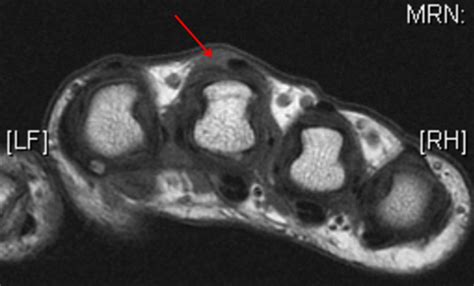

• Order imaging studies, such as X-rays or MRI scans, to visualize the extent of the injury and rule out other potential causes of symptoms.

In some cases, a dynamic ultrasound may be used to observe the movement of the extensor tendons in real-time, providing valuable information for diagnosis and treatment planning.